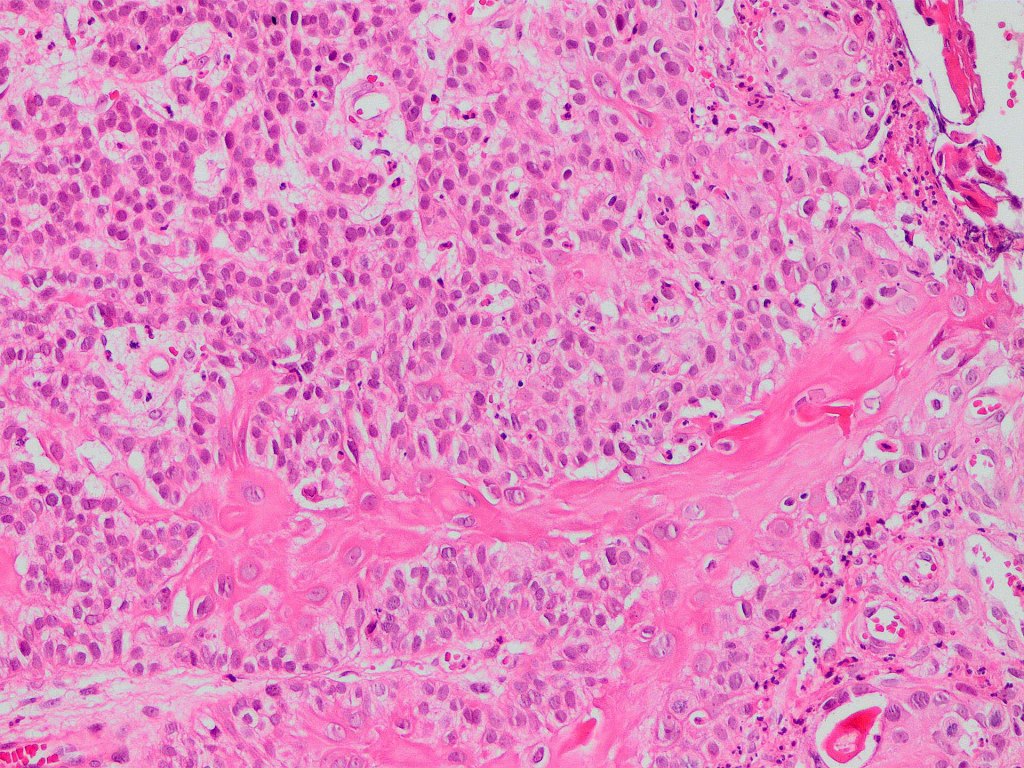

•Biphasic tumor

•Admixture of squamous carcinoma & pleomorphic spindled cell, osteoid, chondroid, MFH-like +/- osteoclast-like giant cells & rarely, smooth muscle, skeletal muscle, myofibroblastic or angiosarcomatous elements